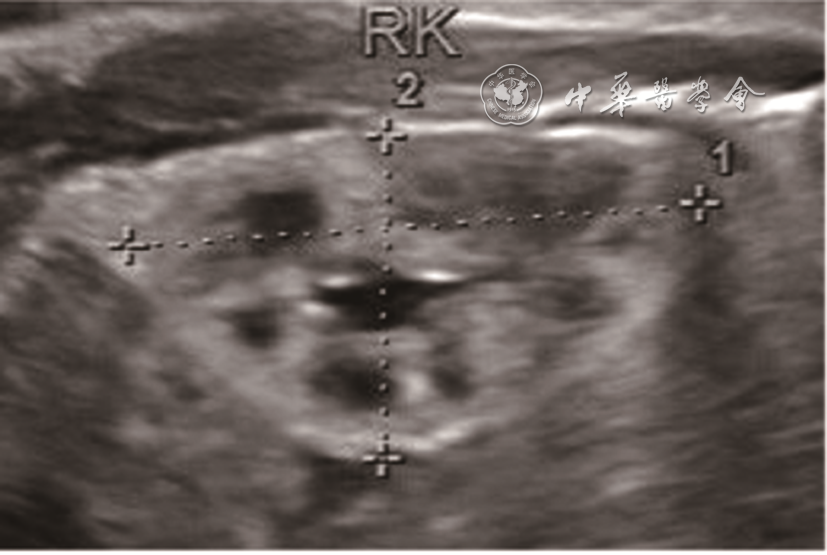

图1 孕33周胎儿肾超声声像图。图a超声声像图示右侧肾体积明显增大,皮髓质分界清晰,皮质回声增强;左侧肾体积轻度增大,皮髓质分界模糊,实质可见多发大小不等的囊性结构;图b为胎儿肾大体观

注:RK为右肾,LK为左肾